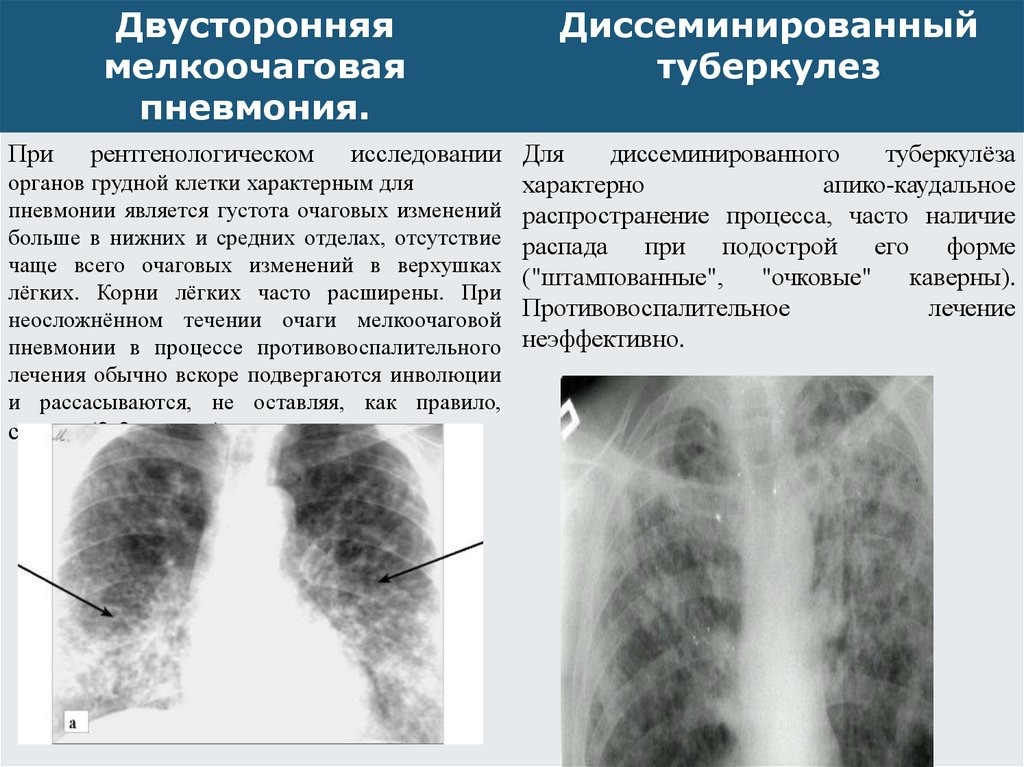

В клинической картине острого гематогенно диссеминированного туберкулеза преобладает